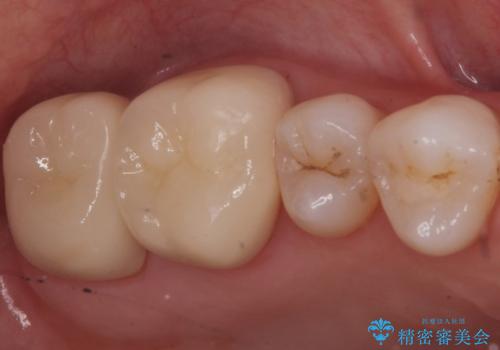

- 銀歯を白くしたいとのことで来院されました。

銀の詰め物を除去した後、その奥にある古い詰め物も除去し完全にむし歯を取り切ったことを確認してからセラミッククラウンを装着していきます。

- 右上67 仮歯+ジルコニアクラウン:11,000+110,000円 右上7/根管治療:保険 ファイバーコア:22,000円費用は治療当時の料金となります